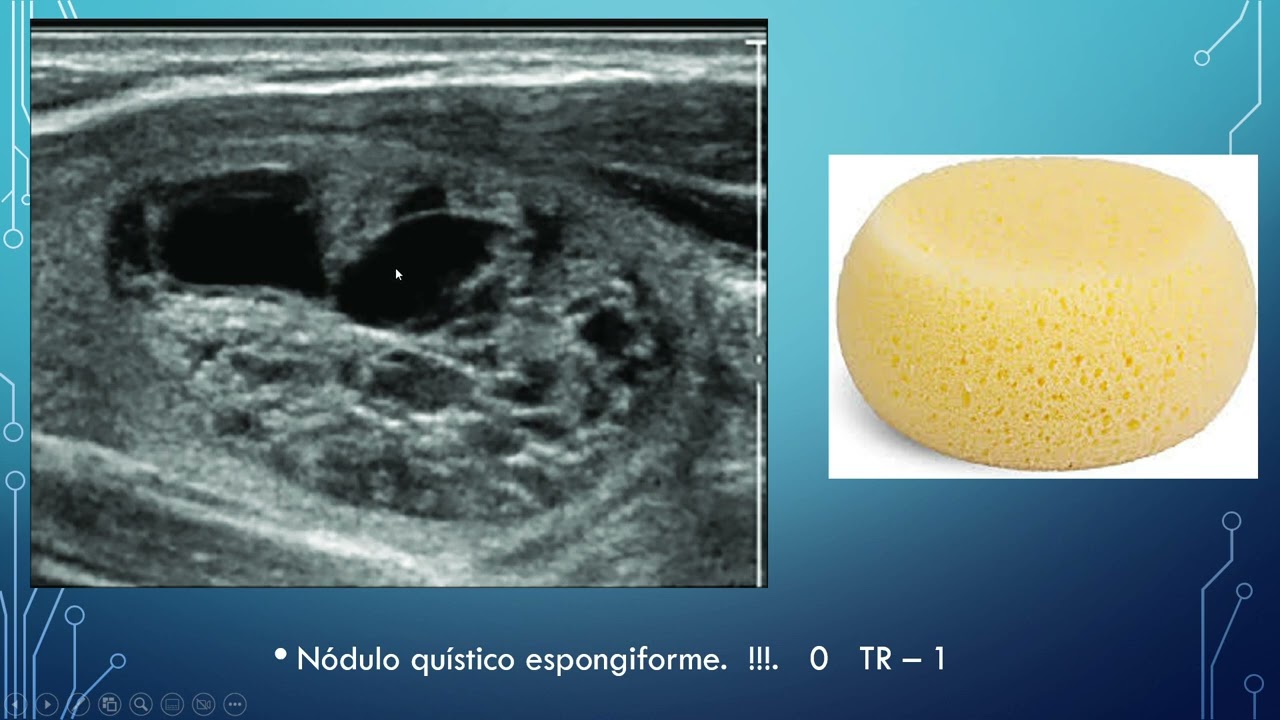

Patología Difusa de la Tiroides: Lo que debemos saber para su abordaje y diagnóstico diferencial.

ECOGRAFIA DE TIROIDES, EVALUACION DE NODULOS, APLICACION TI RADS

ACR TI-RADS para Dummies — Una Guía Práctica Para el Radiólogo

Utilidad clínica del ultrasonido de tiroides y la clasificación TI RADS